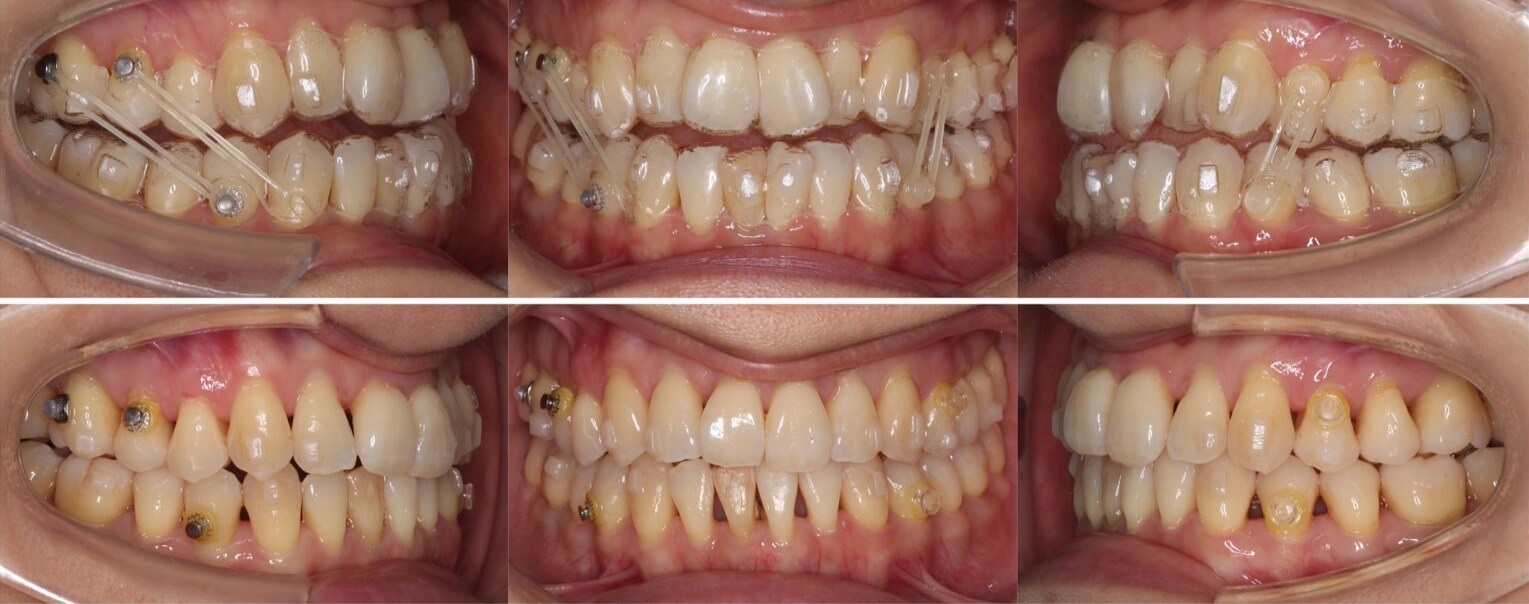

43歳女性・唇側矯正装置・抜歯

ミドルエイジの矯正治療で抜歯方針を選択する場合は、細心の注意を払います。これは、前歯が後方に引き下がりすぎる可能性があるからです。事前に横顔のシミュレーションを確認していただき、ほうれい線が深くなるなどのリスクも承諾の上、治療を開始しました。治療後はバランスの良い横顔になりました。

<症例概要>

主訴:口元の突出

年齢・性別:43歳女性

住まい:千葉県八千代市

症状:上下顎前歯唇側傾斜・正中離開

治療方針:上下左右4番(計4本)

治療装置:唇側矯正装置

固定装置:ナンスホールディングアーチ

治療期間:2年9か月

リテーナー:上下フィックス+プレートタイプ

治療費用:968,000(税込)

代表的副作用:痛み・治療後の後戻り・歯根吸収・歯髄壊死・歯肉退縮

▶︎その他の副作用